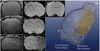

Methods: Transient cerebral ischemia was induced in adult Wistar rats (n=25) followed by IA or intravenous (IV) injection of mesenchymal stem cells (MSCs) labeled with superparamagnetic iron oxide. Cell infusion was monitored in real time with transcranial laser Doppler flowmetry while cellular delivery was assessed with MRI in vivo (4.7 T) and ex vivo (9.4 T).

Results: Successful delivery of magnetically labeled MSCs could be readily visualized with MRI after IA but not IV injection. IA stem cell injection during acute stroke resulted in a high variability of cerebral engraftment. The amount of LDF reduction during cell infusion (up to 80%) was found to correlate well with the degree of intracerebral engraftment, with low LDF values being associated with significant morbidity.